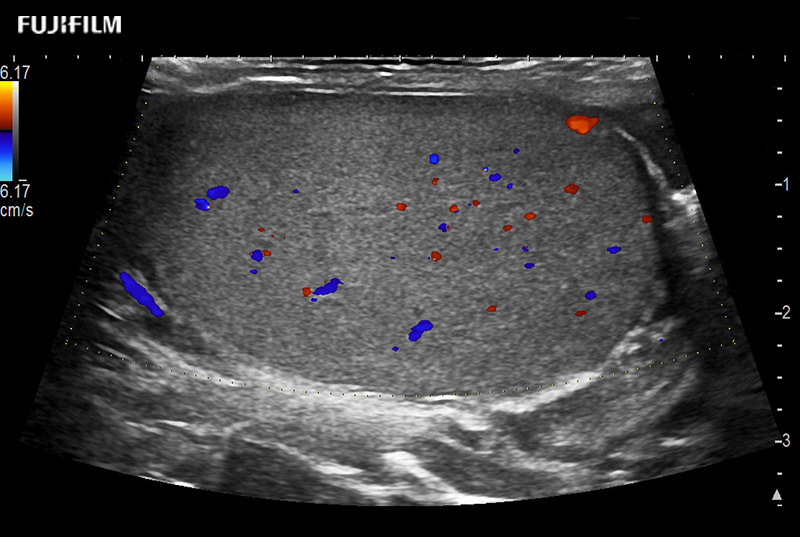

including: B-Mode, Color Doppler, Power Doppler, Fine Flow

– better visualization of tumors to improve understanding of blood flow information